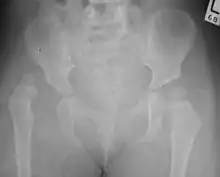

Despite the widespread use of ultrasound, pelvis X-ray is still frequently used to diagnose or monitor hip dysplasia or for assessing other congenital conditions or bone tumors.[43]